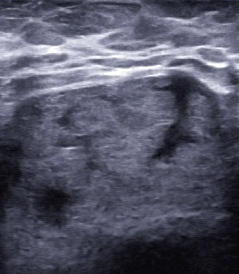

Etwa ein Jahr später wurde die Patientin wieder vorstellig. Sie hatte zwischenzeitlich eine Brustvergrößerung mit Eigenfett vornehmen lassen und bat um Kontrolle einer störenden Abflachung im unteren Bereich der rechten Brust (Abb. 3–5). Die sonografische Untersuchung war unauffällig, lediglich die normale Befundung nach derlei Eingriffen konnte dokumentiert werden (Abb. 6–8).